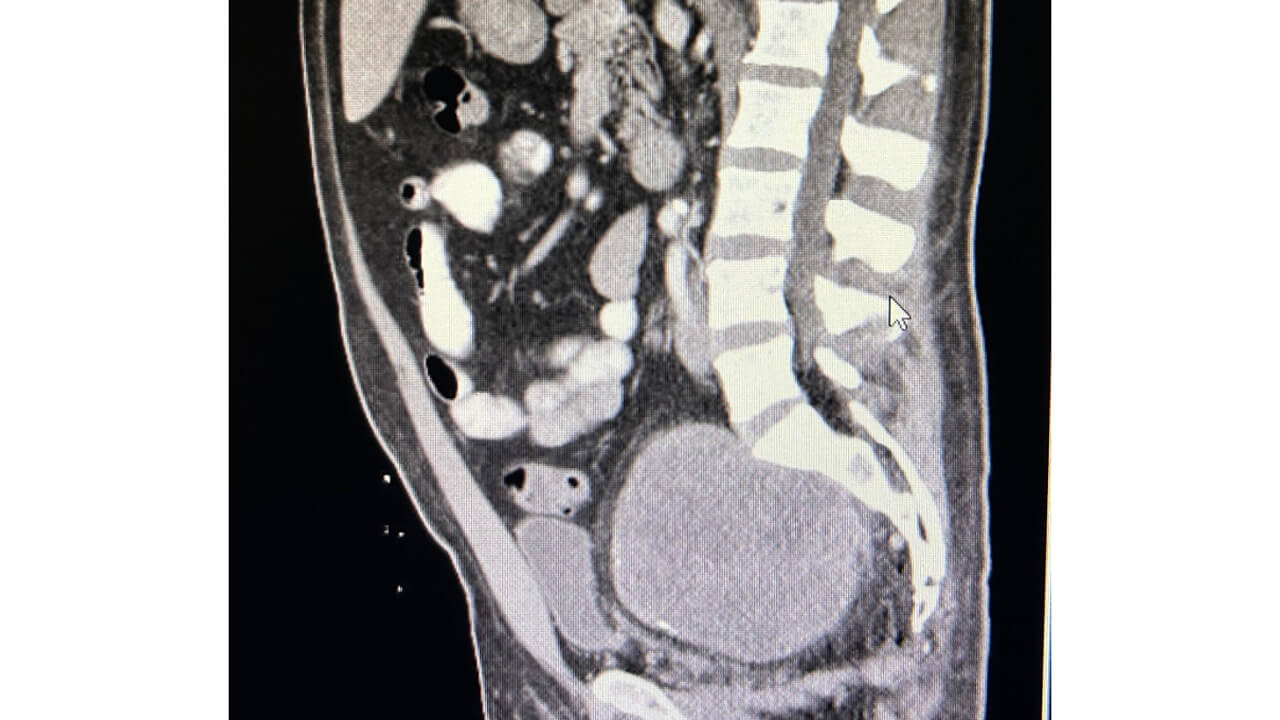

• Figure 3 shows pre-operative CT of abdomen/pelvis with IV contrast which revealed 11 x 8.6 x 9.5cm pelvic mass and 2.7 millimeter enhancing right renal lesion.